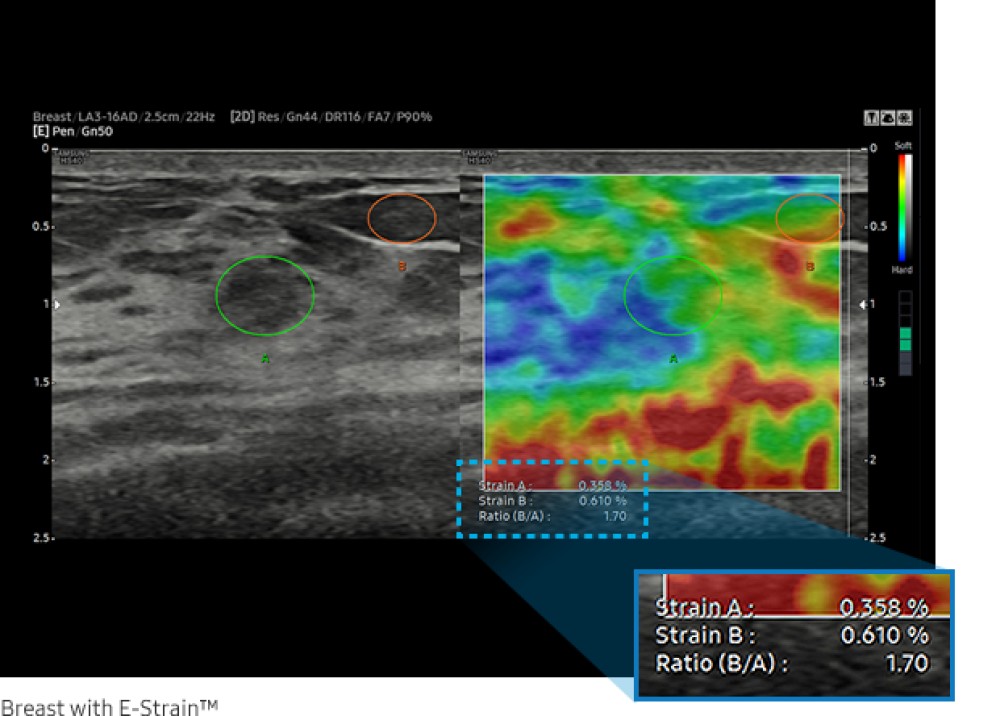

LA3-16A: Geniş zolaqlı lineer array; qarın, muskuloskeletal, pediatrik, kiçik orqanlar və vaskulyar görüntüləmə üçün uyğundur.